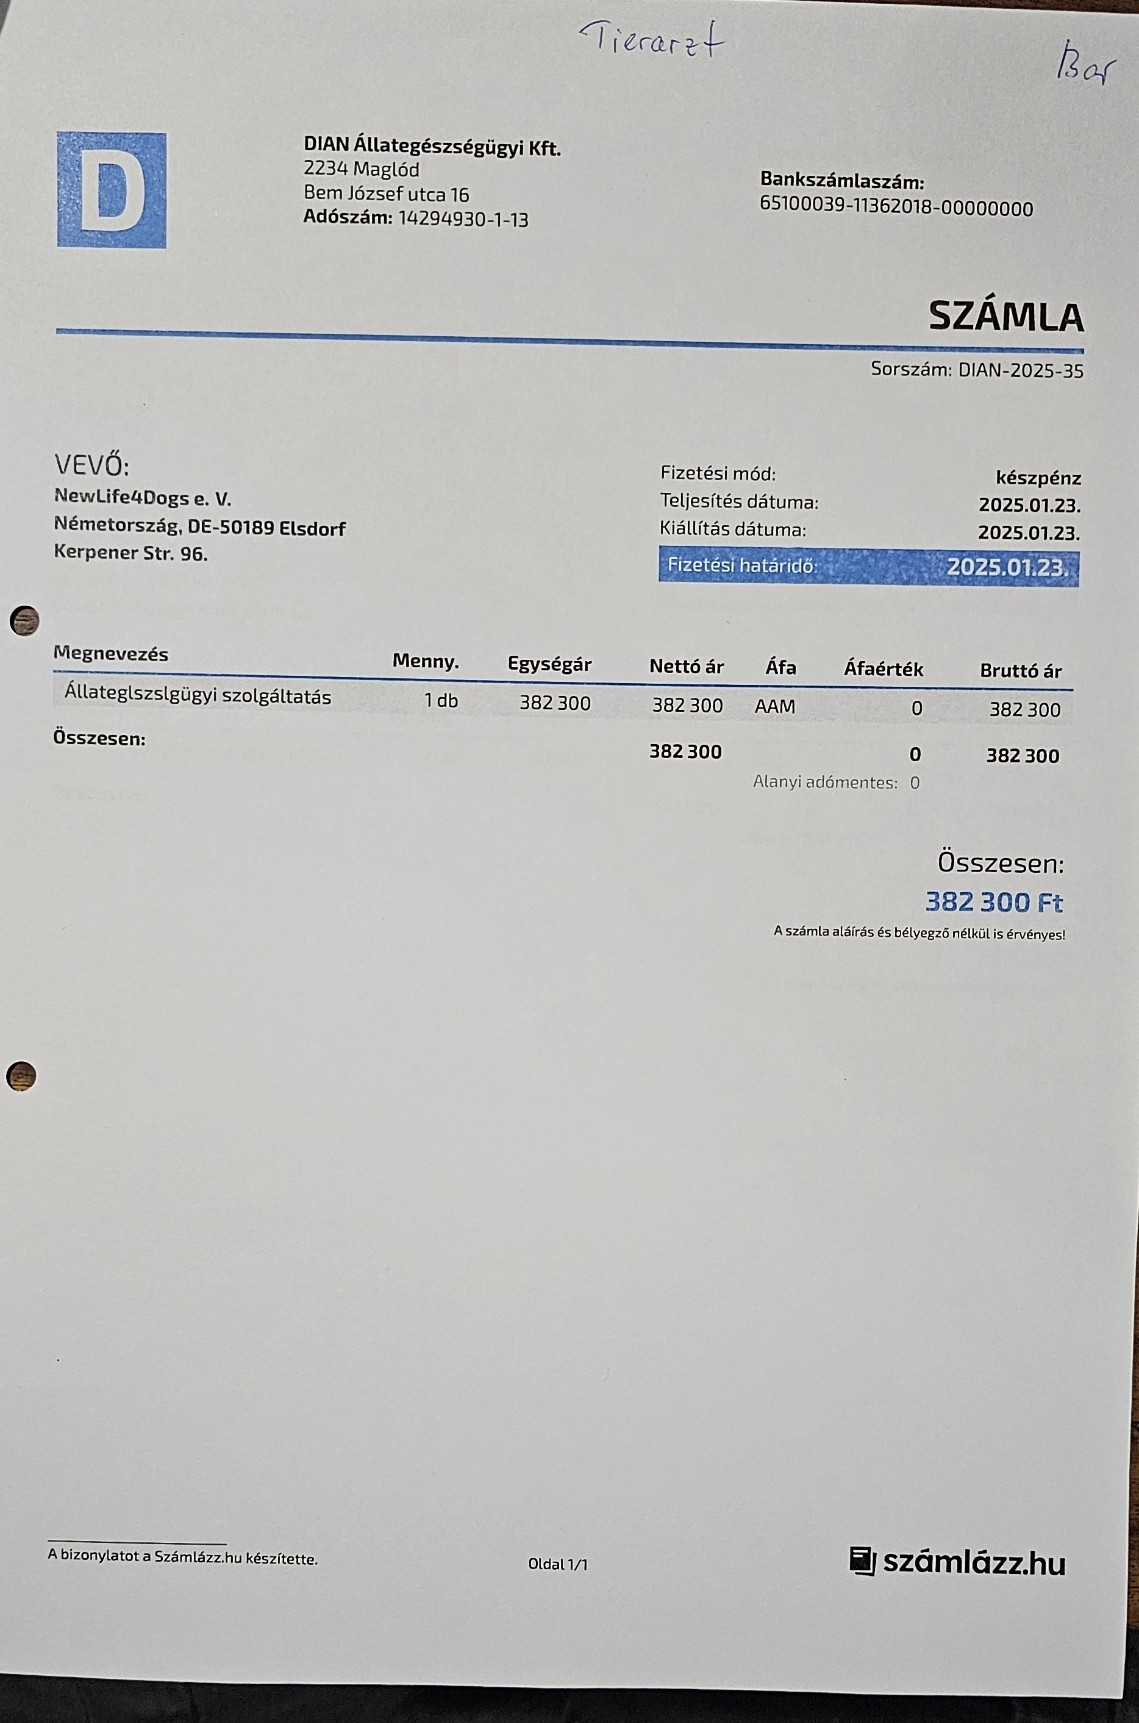

Nachdem die kleine Stella nach mehr als einer Woche die Klinik verlassen durfte, Mussten erneut einige unserer Neuzugänge dringende Not-OP´s und stationäre Aufnahme +ber sich ergehen lassen. So auch der kleine Sidney, den wir schwer verletzt mit gebrochenem Hinterbeinchen auf der Strasse in Nordungarn fanden. Sofortige Untersuchungen, Rüntgenaufnahmen und unverz+gliche Notoperation war erforderlich. Die Operation hat der kleine Mann gut überstanden. Nun benütigt er weitere Medikamente und Vitaminprodukte, damit er einen guten Heilungsprozess durchlaufen kann. Ebenso benütigt er 6 Wochen Zwingerruhe und Physiotherapie.

Auch unser lieber Oskar musste heute notfallmäßig in die Tierklinik. Aus derzeit noch unerklärlichen Gründen kann oskar sich nicht mehr auf seinen Hinterbeinen halten. Natürlich brachten wir ihn sofort in die Klinik. dort wurde er stationär aufgenommen. Nun ist eine MR untersuchung erforderlich, um die Ursache f+r die plützlichen Lähmungserscheinungen zu finden. Auch in der zweiten hälfte des Monats mussten wir wieder hohe Klinikkosten und Tierarztkosten bewältigen. Wir wären extrem erleichtert und dankbar wenn uns der ein oder andere hierbei unterst#tzen würde.